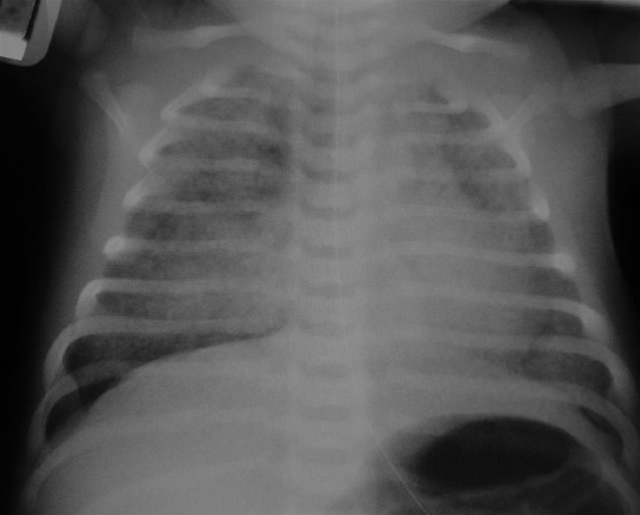

Respiratorisk distress syndrom

• Rtg. thorax viser homogene tætte infiltrater og luftbronkogram